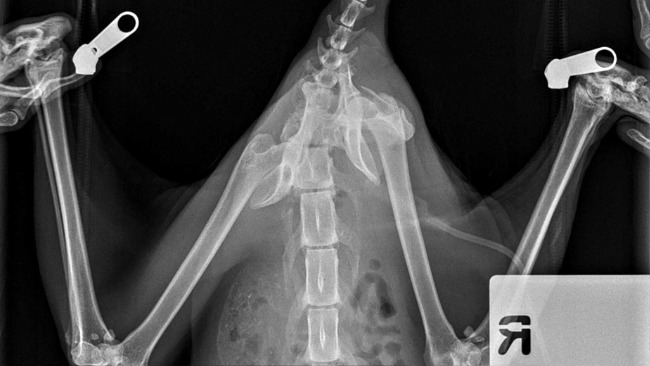

Od tygodni jeździmy z nim codziennie do weterynarza. I od tygodni obserwujemy, jak Desperado desperacko chce żyć. Nie może chodzić z powodu strzaskanej miednicy. Nie można było zdecydować się na operację, dopóki stan ogólny kota na to nie pozwalał.

A przed nim najważniejsza operacja: poskładania kości miednicy i nóg w całość. Operacja odbędzie się w całodobowej klinice. Operował naszego kota będzie doktor Krajewski. Wierzymy, że się uda i że w końcu Desperado stanie na nogi.